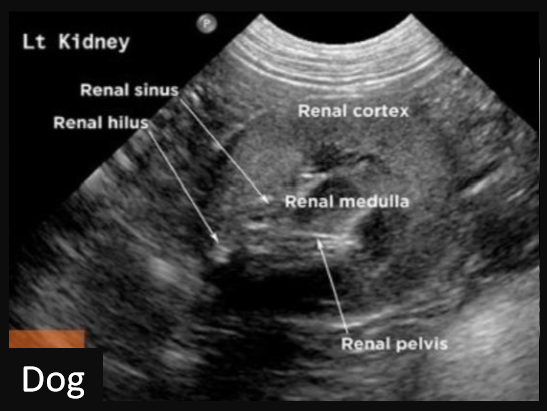

9

Q

Label this frontal/dorsal view kidney ultrasound

A